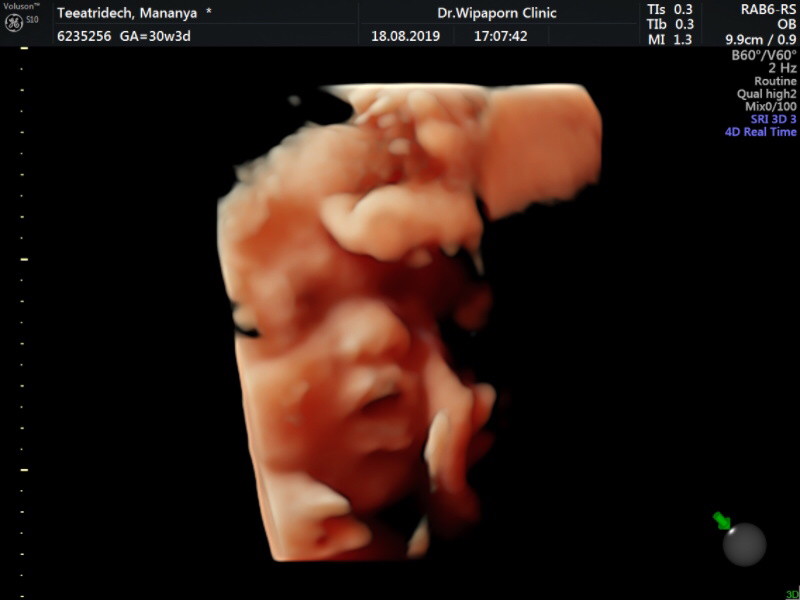

ซาวด์ตอน 30w3d จ้า